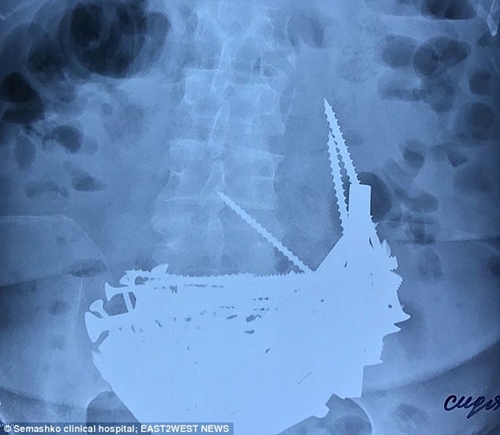

Bà nhập viện do bị sốt nhưng sau khi kiểm tra phim chụp X-quang, các bác sĩ sửng sốt khi phát hiện ra nguyên nhân của hiện tượng này. Có tới hơn 152 vật thể lạ trong bụng của bà cụ về hưu này.

Phim X-quang chụp dạ dày của bà cụ 74 tuổi. |

Các bác sĩ đã tiến hành phẫu thuật và lấy ra rất nhiều đinh dài, ốc vít, bu lông, chốt cửa... có cái dài đến hơn 15cm. Thậm chí còn có cả một chiếc vòng bạc.